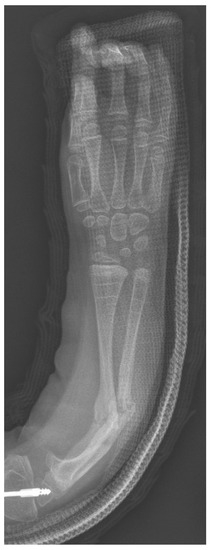

We have attempted to decrease the frequency of wire migration by bending the tip of the ulnar wire into a shepherd’s crook and/or keeping the wire straight and fully tamping it into the cartilage of the olecranon (Figure 3). For the radial wire, we have had a special tamp fashioned (Figure 4) that fits the end of the 0.062” k-wire and confirm both radiographically and under direct vision that the wire is completely buried in the cartilage of the radial styloid. Our current cohort of patients is not large enough and has not been followed long enough to determine if these changes have decreased our wire prominence problems, longer-term follow-up will help to determine this.

Figure 3. Ulnar k-wire buried in the cartilage of the apophysis vs. ulnar wire buried with a crook in the wire.